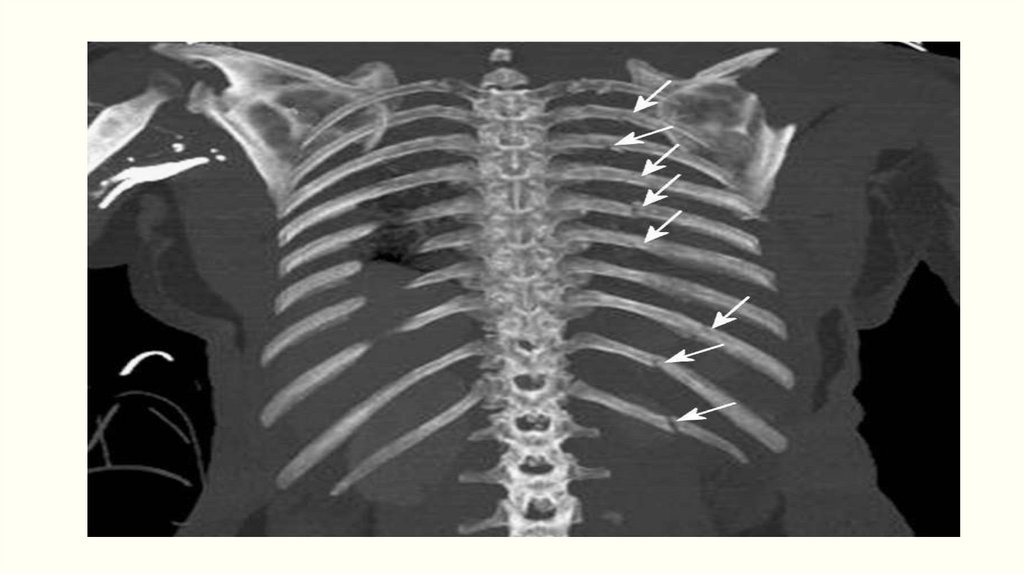

Переломы ребер

Переломы грудины